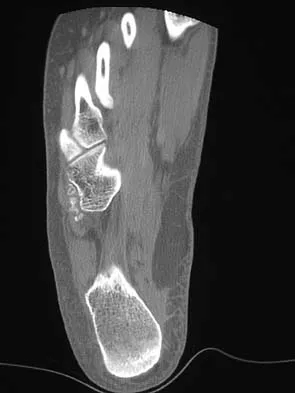

A 28-year-old professional dancer reports a 3-month history of progressive pain in the posterior aspect of the left ankle. Her symptoms are worse when she assumes the en pointe position. Examination reveals tenderness to palpation at the posterolateral aspect of the ankle posterior to the peroneal tendons which is made worse with passive plantar flexion. There is no nodularity, fluctuance, or tenderness of the Achilles tendon. The neurovascular examination is unremarkable. A lateral radiograph and MRI scan are shown in Figures 16a and 16b, respectively. Management should consist of

The imaging studies reveal findings typical of the os trigonum syndrome. This condition results from inflammation between the os trigonum and the adjacent talus. The symptoms of posterior ankle pain are exacerbated by plantar flexion, which stresses the fibrous union between these two bones. Definitive management of the high-level athlete involves excision of the os trigonum from a medial approach, although arthroscopic excision has also been described. The os trigonum is not an intra-articular structure; therefore, ankle arthroscopy is neither diagnostic nor therapeutic. Abramowitz Y, Wollstein R, Barzilay Y, et al: Outcome of resection of a symptomatic os trigonum. J Bone Joint Surg Am 2003;85:1051-1057. Mouhsine E, Crevoisier X, Leyvraz P, et al: Post-traumatic overload or acute syndrome of the os trigonum: A possible cause of posterior ankle impingement. Knee Surg Sports Traumatol Arthrosc 2004;12:250-253.